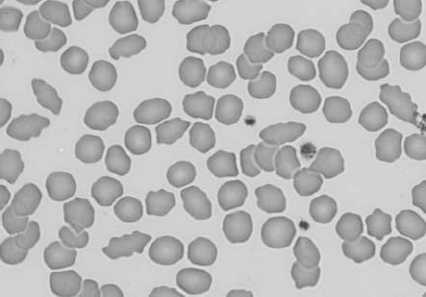

Figure 1.3 Canine blood film showing acanthocytes (also see color section).

Figure 1.4 Canine blood film showing anisocytosis (also see color section).

Figure 1.5 Bovine blood film showing basophilic stippling within a macrocyte as part of the regenerative response (also see color section).

Figure 1.6 Canine blood film showing basophilic stippling due to lead toxicosis (also see color section).

Figure 1.7 Canine blood film showing blister cells due to oxidative damage (also see color section).

Figure 1.8 Canine blood film showing codocytes. Up to 50% codocytes may be normal in a dog (also see color section).

Figure 1.9 Canine blood film showing eccentrocytes due to oxidative damage (also see color section).

Figure 1.10 Canine blood film showing echinocytes I (also see color section).

Figure 1.11 Canine blood film showing echinocytes III (also see color section).

Figure 1.12 Feline blood film showing echinoelliptocytes (also see color section).

Figure 1.13 Canine blood film showing Heinz bodies and ghost cells due to oxidative damage. There are also several polychromatophils (also see color section).

Figure 1.14 Canine blood film stained with new methylene blue, to demonstrate Heinz bodies (also see color section).

Figure 1.15 Canine blood film showing keratocytes and schizocytes (erythrocyte fragments) due to fibrin strand injury. A codocyte and a polychromatophil also appear in the field (also see color section).

Figure 1.16 Feline blood film showing Mycoplasma hemofelis organisms (hemobartonellosis). Organisms are not always visible in blood smears from infected cats (also see color section).

Figure 1.17 Canine blood film showing several macrocytes (also see color section).

Figure 1.18 Canine blood film showing a metarubricyte There is also a polychromatophilic macrocyte in the field (also see color section).

Figure 1.19 Canine blood film showing microcytic, hypochromic erythrocytes consistent with iron deficiency anemia. There are two polychromatophils in the field, indicating that the anemia is regenerative (also see color section).

Figure 1.20 Canine blood film showing two macrocytes with nuclear remnants (also see color section).

Figure 1.21 Bovine (calf) blood film showing marked poikilocytosis (normal?) (also see color section).

Figure 1.22 New methylene-blue-stained Canine blood film showing reticulocytes (also see color section).

Figure 1.23 Canine blood film showing rouleaux formation (also see color section).

Figure 1.24 Canine blood film showing spherocytosis and polychromasia due to immune-mediated hemolytic anemia (also see color section).

Figure 1.25 The red blood cell cytoskeleton.